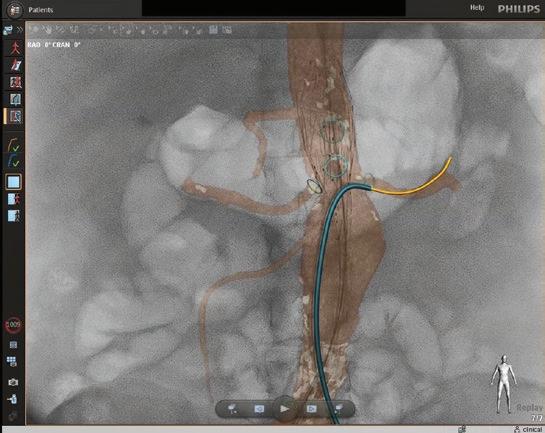

Instead of the ionizing radiation of fluoroscopy, FORS technology uses light refracted through optical fibers to provide 3D tracking of endovascular guidewires, catheters and devices. FORS technology has the potential to reduce a patient’s radiation exposure by as much as 75% during endovascular complex aortic aneurysm repair.

Fiber Optic RealShape technology enhances visibility as the operator moves devices through the arteries. The 3D images enable the team at the Center for Complex Aortic Disease to view progress and movement from any angle.

Imaging advantages

In addition to reducing the need for fluoroscopy, FORS technology enhances the visibility as the operator moves devices through the arteries. The real-time images produced are three dimensional, so the EVAR team can view progress and movement from any angle. The technology also allows for zooming in and having multiple projections on-screen at once.

“This enables me to always keep the full extent of the guidewire in my field of vision,” Schanzer said. “Then I can advance the FORS catheter over the wire to get it in position. The FORS system shows which portion of the guidewire or catheter is in front of the other, making all endovascular interventions easier and safer.”

The FORS images are displayed on top of, and in alignment with, anatomical patient images created through digital subtraction angiography (DSA) or computed tomography (CT), both of which are black and white. With DSA or CT images alone, it can be difficult to determine the exact placement of the catheter, but with FORS technology, it can be seen in color in the foreground.

“The system is very intuitive and truly represents a new era in device guidance,” Schanzer said, adding that having a color image has an additional benefit. “Until I started using FORS, I hadn’t realized how much operator fatigue there is when you’re only looking at different shades of gray to visualize everything. It’s become very apparent to me that the bright yellow and blue on top of the gray background really decreases that strain, especially when you’re looking at previous stent grafts and wires.” ◼